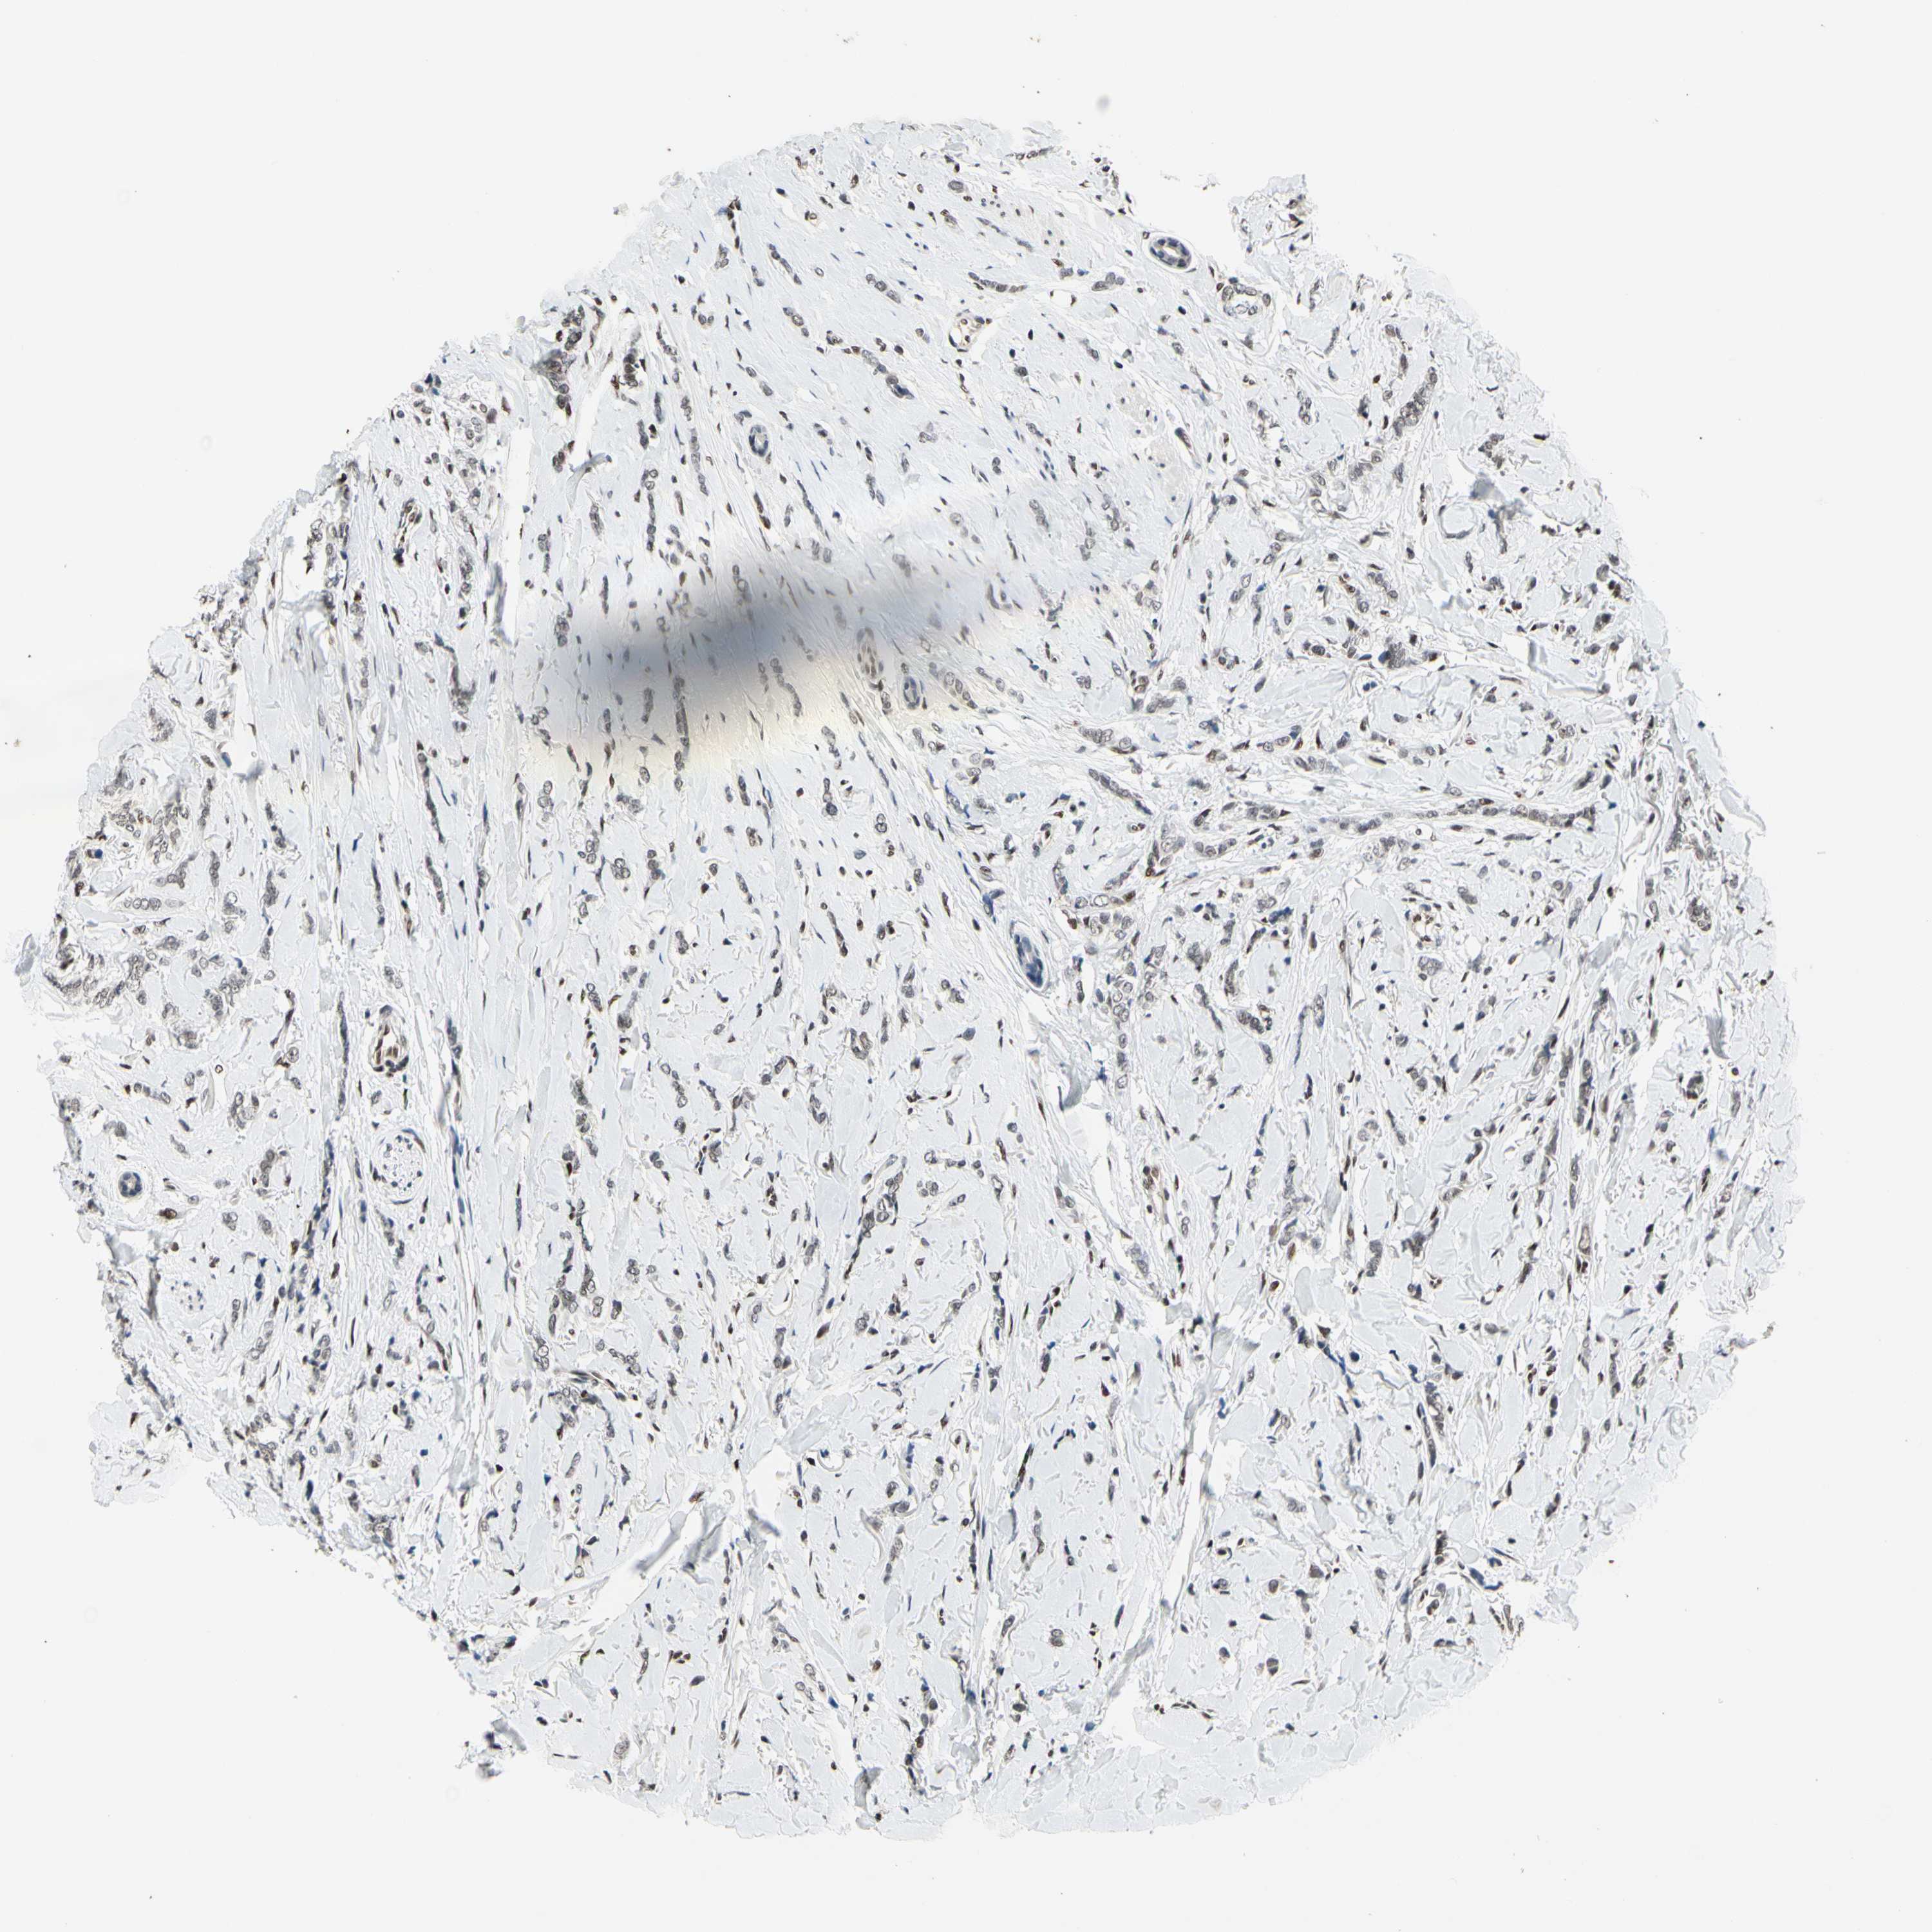

CANCER BREAST CANCER Show tissue menu

BRCA TCGA BRCA VALIDATION PROTEIN EXPRESSION

ANTIBODIES

AND

VALIDATION